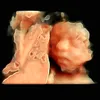

C ơi cho e xin ảnh này vs ạ

2025-08-13 13:48:46

Cho e xXin ảnh này shoppp ơi

2025-09-10 00:43:44